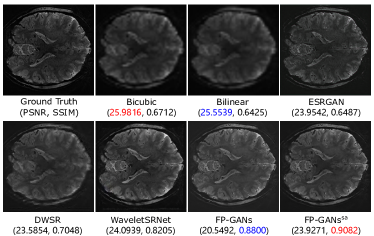

Figure 6: Visual comparison of detail recovery performance on MultiRes_7T dataset. The images are gained with super-resolution scale factor ×4absent4\times 4. Red and blue indicate the best and the second best performance, respectively.

Peak signal noise ratio (PSNR) and structural similarity index (SSIM) have been commonly applied in many super-resolution researches as standard evaluation metrics. Nevertheless, it was found that high PSNR doesn’t guarantee a high visual quality during experiment. As illustrated in Figure 11, Bicubic and Bilinear rank higher in PSNR, but the result of other methods are visually better from human perspective. Study[32] also claimed that PSNR fails to assess image quality accurately with respect to human visual system. Under this circumstance, Fréchet Inception Distance (FID), calculating the feature distance of two images, is utilized to assess the perceptual quality of SR MR images. In summary, PSNR and SSIM are applied to measure the objective quality of images. FID is utilized to assess the visual quality from human perception.

Figure 11: Comparison of quantitative value and visual quality. Red and blue indicate the best and the second best performance, respectively.

As illustrated in Figure 6, the interpolation based methods produce over-smooth results. GAN based method—ESRGAN reproduces rich textures though, the result loses its coherency with the input. FP-GANs recovers finer anatomical structure with shaper and clearer textures while remaining consistency. To further examine the detail capture ability, difference heatmap, reflecting absolute difference between generated image and corresponding ground truth, is utilized as Figure 7 shows. It can be apparently observed that there is less difference in the heatmap of FP-GANs and FP-GANssa than the competing methods. This confirms the detail sensitivity of the proposed structure.